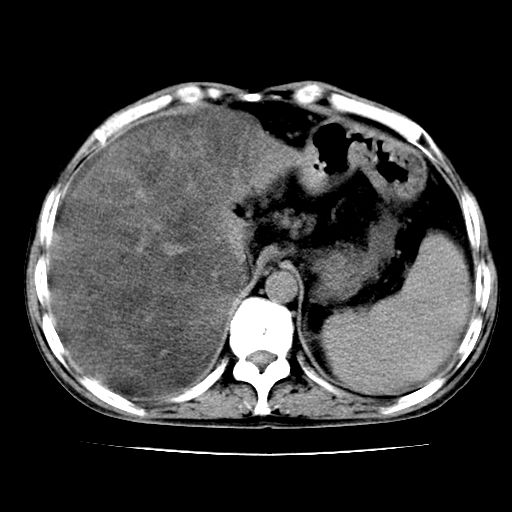

男,55岁,发现“肝硬化”5年,现腰疼、腹胀10余日,巩膜黄染、腹稍胀,肝肋下3指,质硬无压疼,移动性+,血生化:总胆、直胆、间胆均升高。

肝硬化,脾大,腹水

脂肪肝

肝内多发低密度灶(建议增强扫描除外肝癌)

肝脾肿大,脂肪肝,腹水。建议增强除外肝癌。